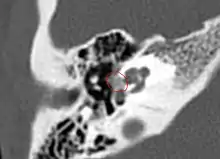

Otosclerosis on CT can be graded using the grading system suggested by Symons and Fanning.[21]

- Grade 1, solely fenestral;

- Grade 2, patchy localized cochlear disease (with or without fenestral involvement) to either the basal cochlear turn (grade 2A), or the middle/apical turns (grade 2B), or both the basal turn and the middle/apical turns (grade 2C); and

- Grade 3, diffuse confluent cochlear involvement (with or without fenestral involvement).

CT scan of otosclerotic focus in the anterior footplate